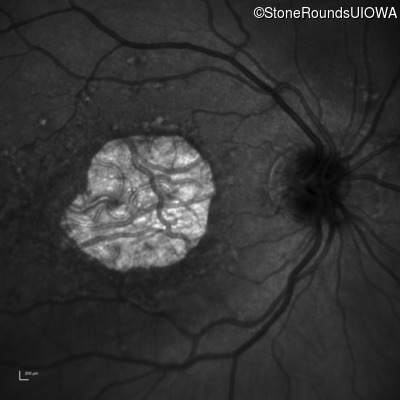

Infrared Fundus Photograph - Right - 20/160 -1

Exemplar